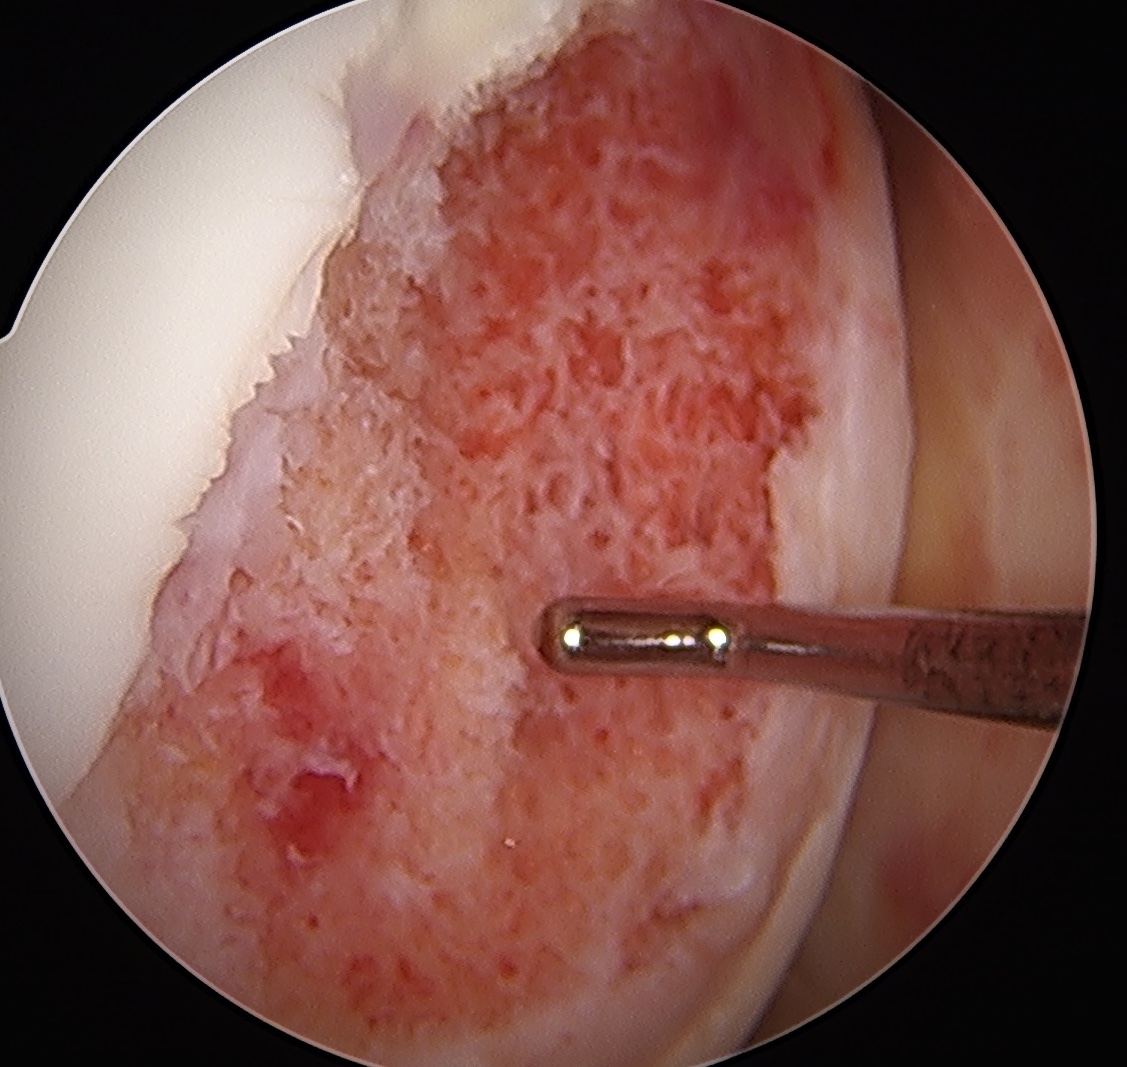

Grade 1: Softening and swelling of the cartilage

Grade 2: Partial thickness defect < 1.5 cm in diameter

Grade 3: Fissuring to subchondral bone, > 1.5 cm in diameter

Grade 4: Exposed subchondral bone

Issue - focus on size of cartilage lesion rather than depth

ICRS / International Cartilage Research Society Arthroscopy Classification

Grade I: Nearly normal - soft indentation / superficial fissures and cracks

Grade II: Abnormal - cartilage lesions < 50% of cartilage depth

Grade III: Severely abnormal - cartilage lesions > 50% of cartilage depth

Grade IV: Severely abnormal - cartilage lesion down to subchondral bone

Grade 0 / normal

Grade I: soft cartilage, superficial fissures

Grade II: cartilage lesion < 50%

Grade III: cartilage lesion > 50%

Grade IV: cartilage lesion down to subchondral bone